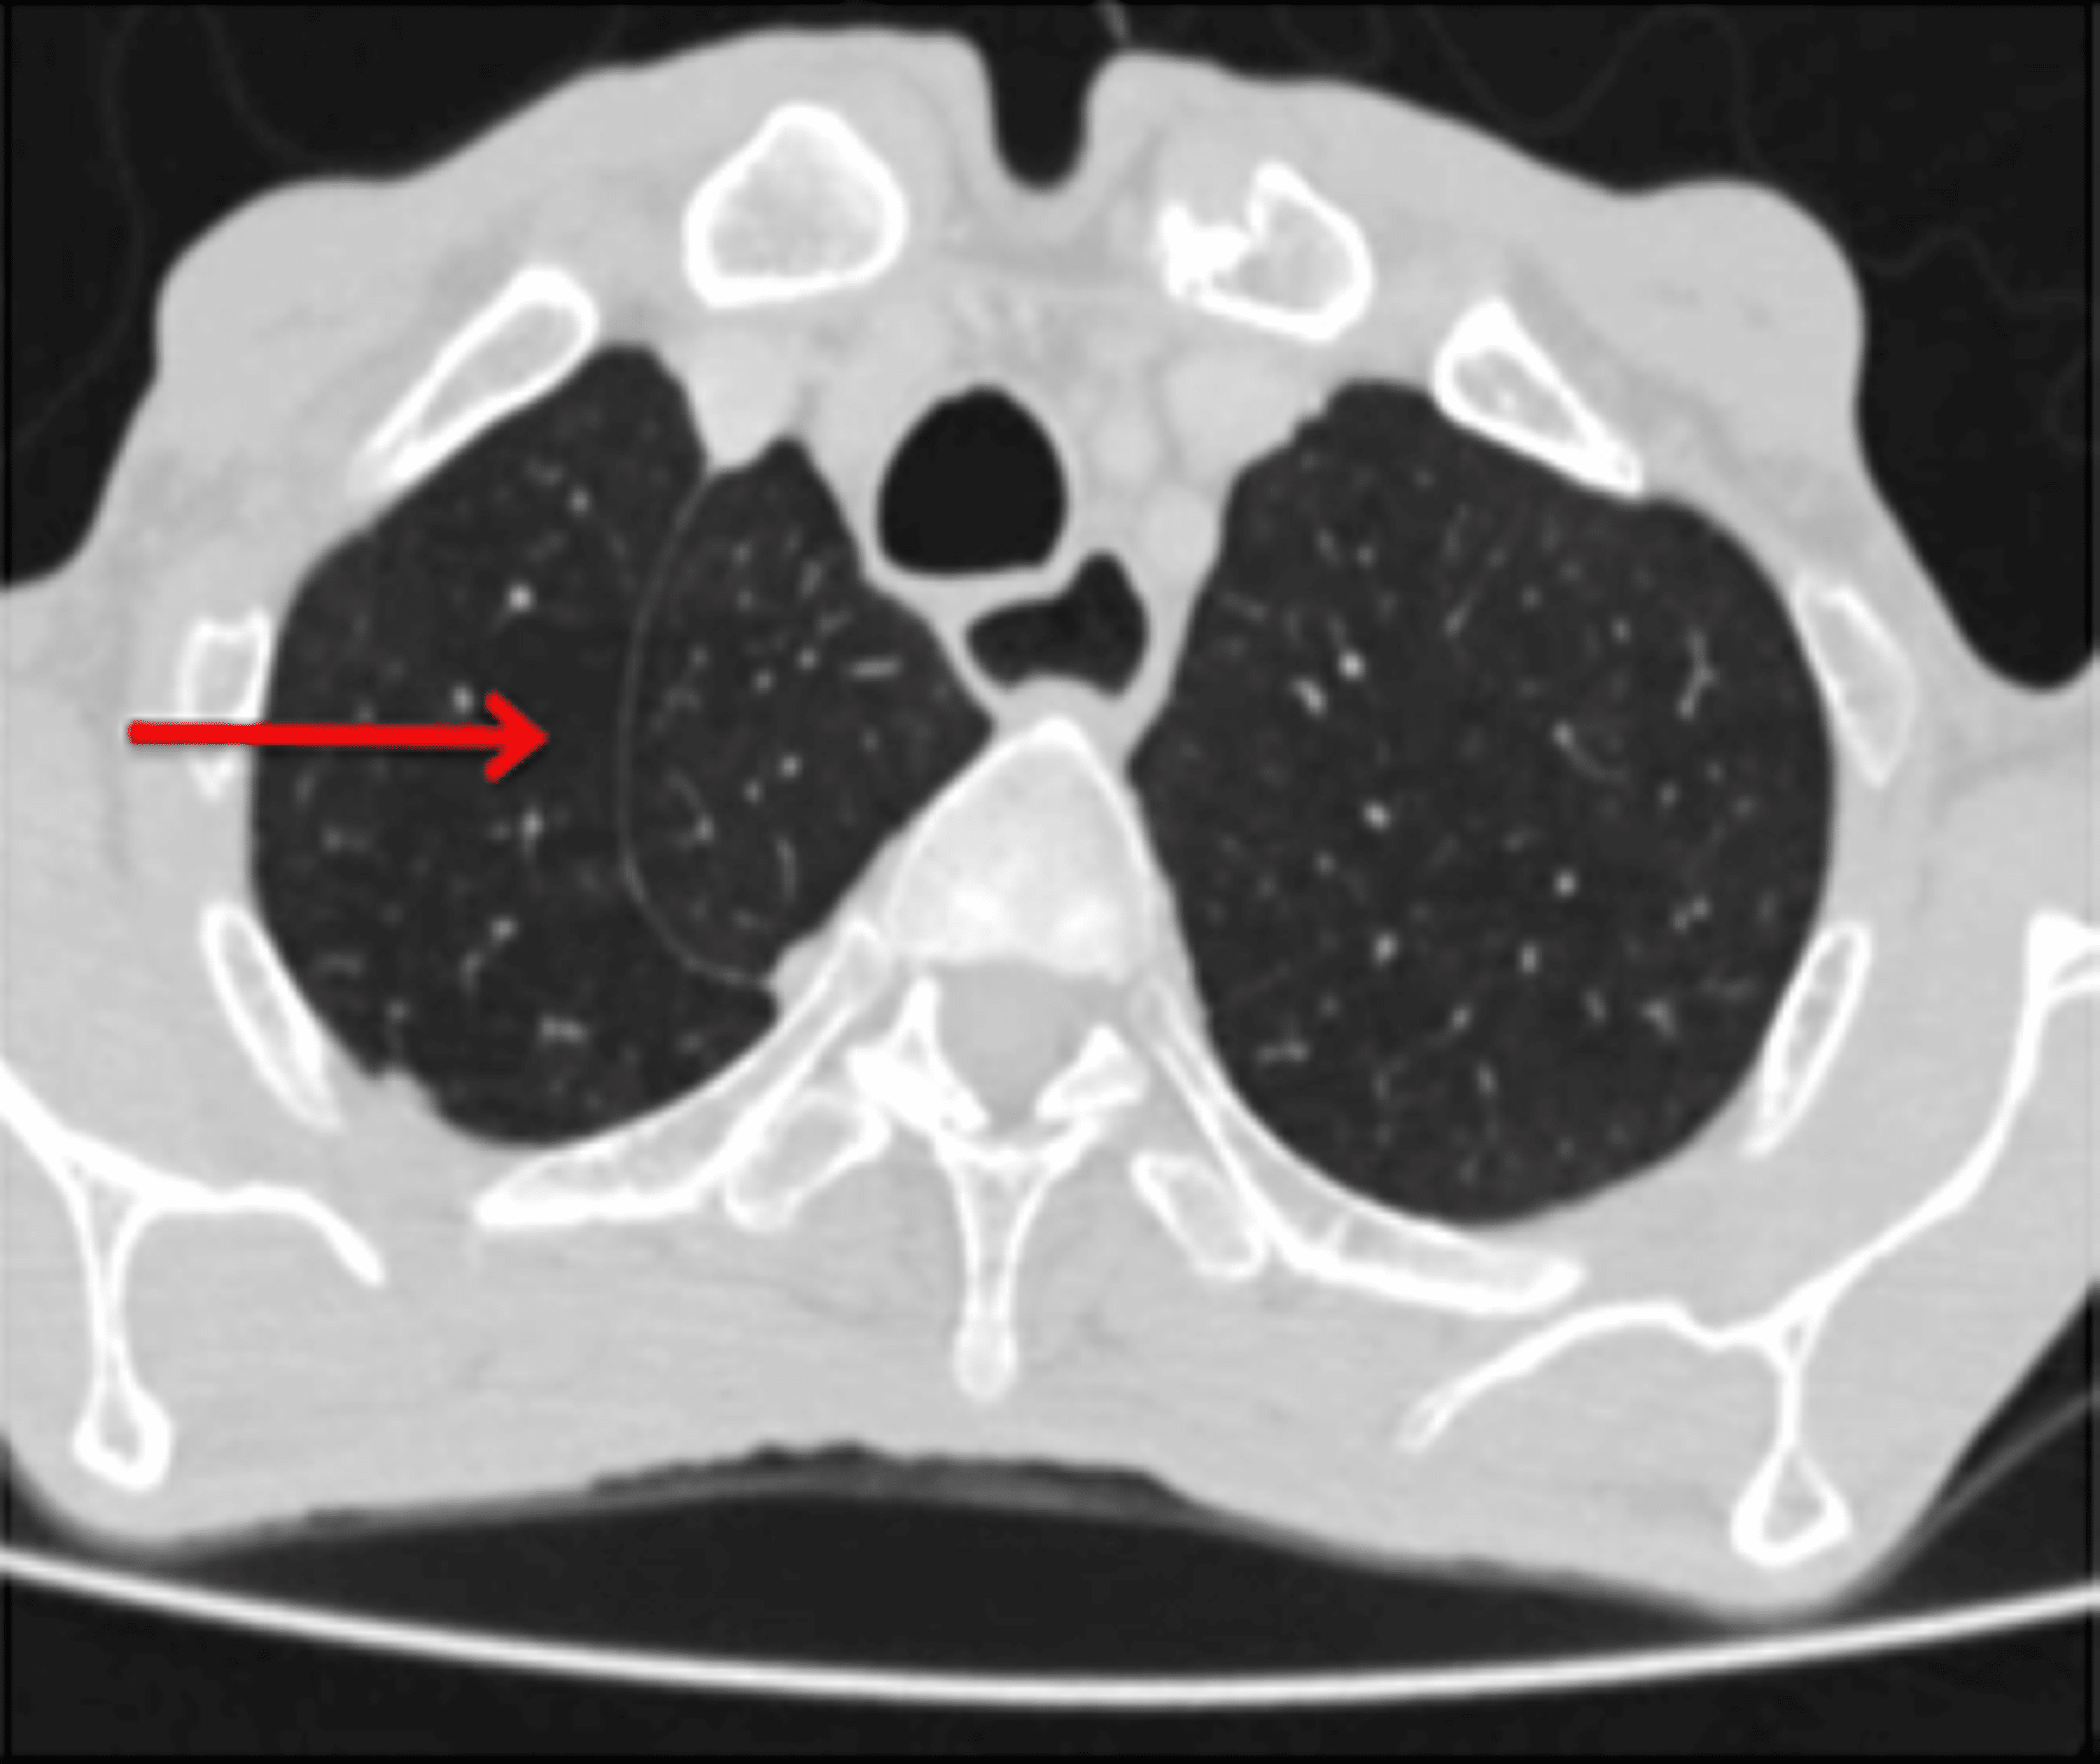

From www.frontiersin.org

Frontiers A pulmonary nodule mislocated in “dorsal” segment due to Accessory Pulmonary Fissures This article has been cited by: In our case, 2 right middle accessory veins drained at the caj, at the level of the. Find out how to distinguish them from fibrotic. Furthermore, old pulmonary lung changes, cardiac insufficiency, atelectasis and pleural effusions can mask the new changes resulting from the current. Anomalous drainage of accessory pulmonary veins are described. Refilwe. Accessory Pulmonary Fissures.